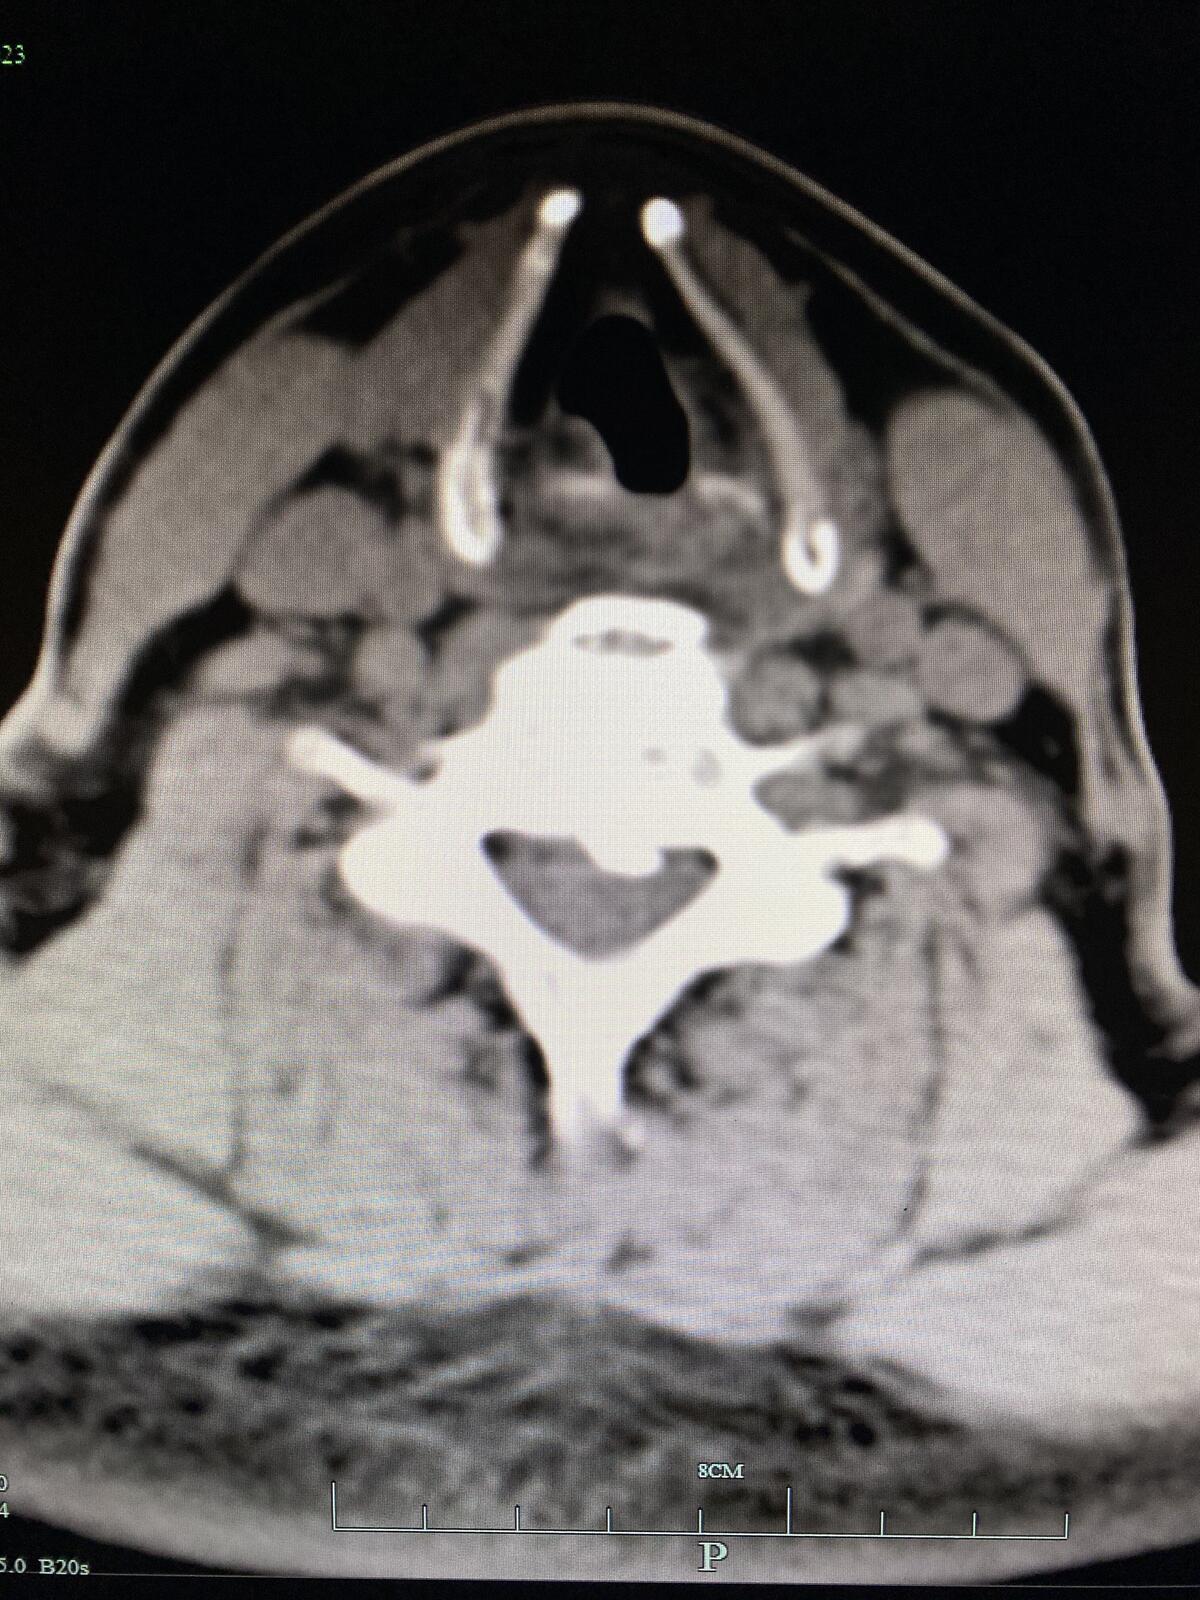

CT显示颈5-6层面后纵韧带骨化及大量骨赘

CT平扫显示压迫脊髓的骨化物